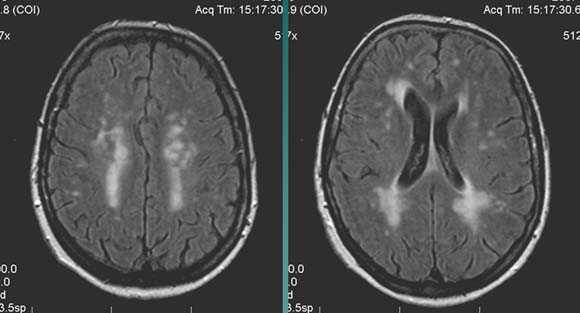

Характерным проявлением ДЭП на МР-томограммах является наличие множественных очагов глиоза.

В белом веществе левой лобной и обеих теменных долей, преимущественно субкортикально, выявлены множественные мелкие очаги хронической ишемии (большинство локализованных в бассейне правой средней мозговой артерии).

Проявлением хронической ишемии является также развитие выраженных дистрофических изменений белого вещества паравентрикулярной локализации - лейкоареоз.

Выраженные дистрофические изменения белого вещества паравентрикулярной локализации - лейкоареоз.